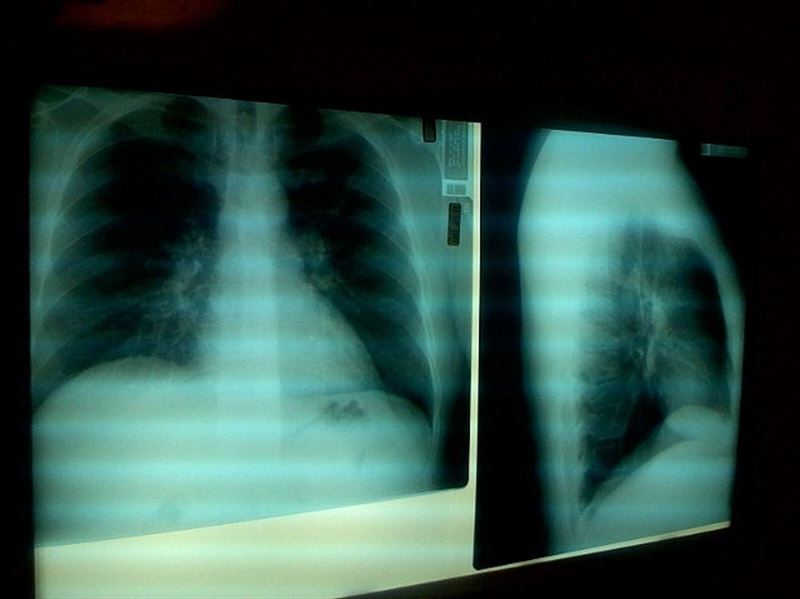

fotonoticia_20160615130130_800La infección más frecuente en el paciente pluripatológico, es decir aquel que sufre dos o más enfermedades crónicas, es la neumonía, que es la primera causa infecciosa de alta hospitalaria en los Servicios de Medicina Interna y la primera causa de mortalidad infecciosa aguda en este grupo, seguida de otras como la septicemia por infecciones urinarias, del tracto biliar e intraabodominales, y las infecciones del sistema nervioso.